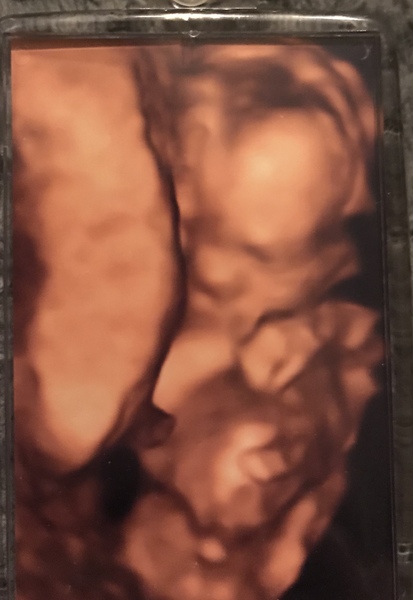

Here he is..my little boy! Not the clearest picture as it’s a key ring and it was only a 4d peek as he’s still so small. I’ll have to show dp with my thumb over the bottom Grin

And I’m hoping so @Giraffe888! Good luck with your scan, it seems like ages to wait. I had no private scans with dd and I’ve had about 3 so far this time..

@chinks123 that’s amazing 💙 I wish I’d asked them to do a quick 4D look at our private scan! X

Awww what a cute photo @chinks123! I can't imagine having to try and keep the sex secret from my OH 😂

@Giraffe888 Thankyou, it came included in the price but was literally only for 1 minute.

I’ve never had a 4d scan before (well we tried with dd but she wouldn’t face us-cost a fortune and I cried for hours.) I would only go to a place now where they would rescan if baby wasn’t playing ball. I still had to pay for dds and I got about 10 pictures of an ear...